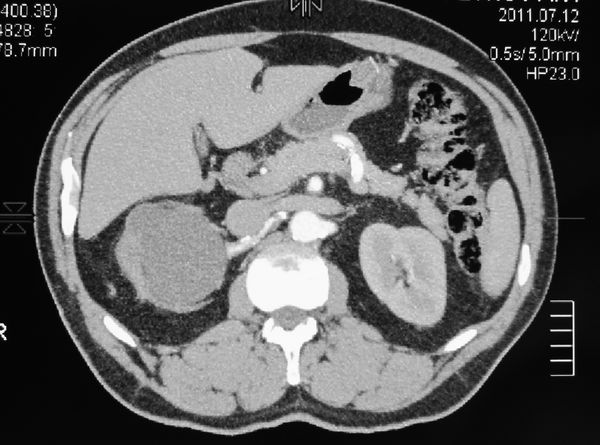

Гидронефротическая трансформация правой почки. Паренхима источнена. ее практически нет.

Удаленная почка.